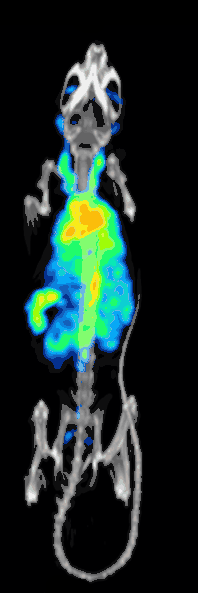

Preclinical or small-animal Single Photon Emission Computed Tomography (SPECT) is a radionuclide based molecular imaging modality for small laboratory animals[1] (e.g. mice and rats). Although SPECT is a well-established imaging technique that is already for decades in use for clinical application, the limited resolution of clinical SPECT (~10 mm) stimulated the development of dedicated small animal SPECT systems with sub-mm resolution. Unlike in clinics, preclinical SPECT outperforms preclinical coincidence PET in terms of resolution (best spatial resolution of SPECT - 0.25mm,[2] PET ≈ 1 mm[3][4] ) and, at the same time, allows to perform fast dynamic imaging of animals (less than 15s time frames[5]).

SPECT imaging requires administration of small quantities of γ-emitting radiolabeled molecules (commonly called "tracers") into the animal prior to the image acquisition. These tracers are biochemically designed in such a way that they accumulate at target locations in the body. The radiation emitted by the tracer molecules (single γ-photons) can be detected by gamma detectors and, after image reconstruction, results in a 3-dimensional image of the tracer distribution within the animal. Some key radioactive isotopes used in preclinical SPECT are 99mTc, 123I, 125I, 131I, 111In, 67Ga and 201Tl.

Preclinical SPECT plays an important role in multiple areas of translational research[6] where SPECT can be used for non-invasive imaging of radiolabeled molecules, including antibodies, peptides, and nanoparticles. Among major areas of its applications are oncology, neurology, psychiatry, cardiology, orthopedics, pharmacology and internal medicine.